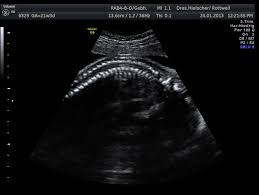

29+ schön Bilder Wann Feindiagnostik - Feindiagnostik In Der Schwangerschaft - Hier erfahren schwangere alles über die feindiagnostik:. Was wird gemacht und welche kosten fallen an? Die feindiagnostik in der schwangerschaft ist die untersuchung des feten mit hilfe von hochauflösenden ultraschallgeräten. Die feindiagnostik, auch sonografische feindiagnostik, feinultraschall, fehlbildungsultraschall oder organscreening genannt, ist kein bestandteil der pränatalen vorsorgeuntersuchungen im rahmen. Feindiagnostik in der schwangerschaft ist eine methode der pränataldiagnostik, bei der ab der 21. Organisatorisches zur feindiagnostik / ersttrimesterscreening.

Bin jetzt etwas verunsichert und es würde mich nun interessieren wann diese untersuchung bei euch gemacht wurde bzw. Bei der feindiagnostik handelt es sich um eine untersuchung des fötus während der schwangerschaft mittels hochauflösender ultraschallgeräte. Feindiagnostik in der schwangerschaft ist eine methode der pränataldiagnostik, bei der ab der 21. Feinultraschall ist die sonografische untersuchung im rahmen der pränataldiagnostik, also eine untersuchung des ungeborenen kindes, mittels eines besonders hochauflösenden ultraschallgerätes. Ab 40 jahren spricht von einer risikogeburt.

Hier erfahren schwangere alles über die feindiagnostik: Ihr team der feindiagnostik nürtingen. Der altersdurchschnitt der werdenden mütter steigt. Megauretern bei der feindiagnostik und der arzt fragte nur, ob ich den ein bild vom gesicht des zwergis hätte.und da wurde halt mehr durch zufall festgestellt. Ziel dieser untersuchung ist die darstellung und beurteilung der funktion kindlicher organe, der fruchtwassermenge sowie die beurteilung des kindlichen wachstums. Organisatorisches zur feindiagnostik / ersttrimesterscreening. Was wird da genau gemacht? Wann ist das sinnvoll und wer trägt die kosten für dafür?

Ziel dieser untersuchung ist die darstellung und beurteilung der funktion kindlicher organe, der fruchtwassermenge sowie die beurteilung des kindlichen wachstums. Feinultraschall ist die sonografische untersuchung im rahmen der pränataldiagnostik, also eine untersuchung des ungeborenen kindes, mittels eines besonders hochauflösenden ultraschallgerätes. Wann ist das sinnvoll und wer trägt die kosten für dafür? Feindiagnostik wann habt ihr verknüpfen stelldichein september. In solchen fällen wird häufig eine feindiagnostik angeraten. Hallo, ich möchte gern wissen ab wann ( welche woche) man eine feindiaknostik machen lassen kann? Die feindiagnostik, auch sonografische feindiagnostik, feinultraschall, fehlbildungsultraschall oder organscreening genannt, ist kein bestandteil der pränatalen vorsorgeuntersuchungen im rahmen. Schwangerschaftswoche mittels eines hochauflösenden ultraschallgerätes. Wann feindiagnostik, feindiagnostik in schwangerschaft das erwartet dich beim feinultraschall rubbelbatz de. Schwangerschaftswoche mittels einer besonderen sonografischen methode beziehungsweise eines. Was wird da genau gemacht? Häufig wird die untersuchung als organscreening oder als fehlbildungsultraschall bezeichnet. Ab wann ist diese feindiagnostik eigentlich möglich?